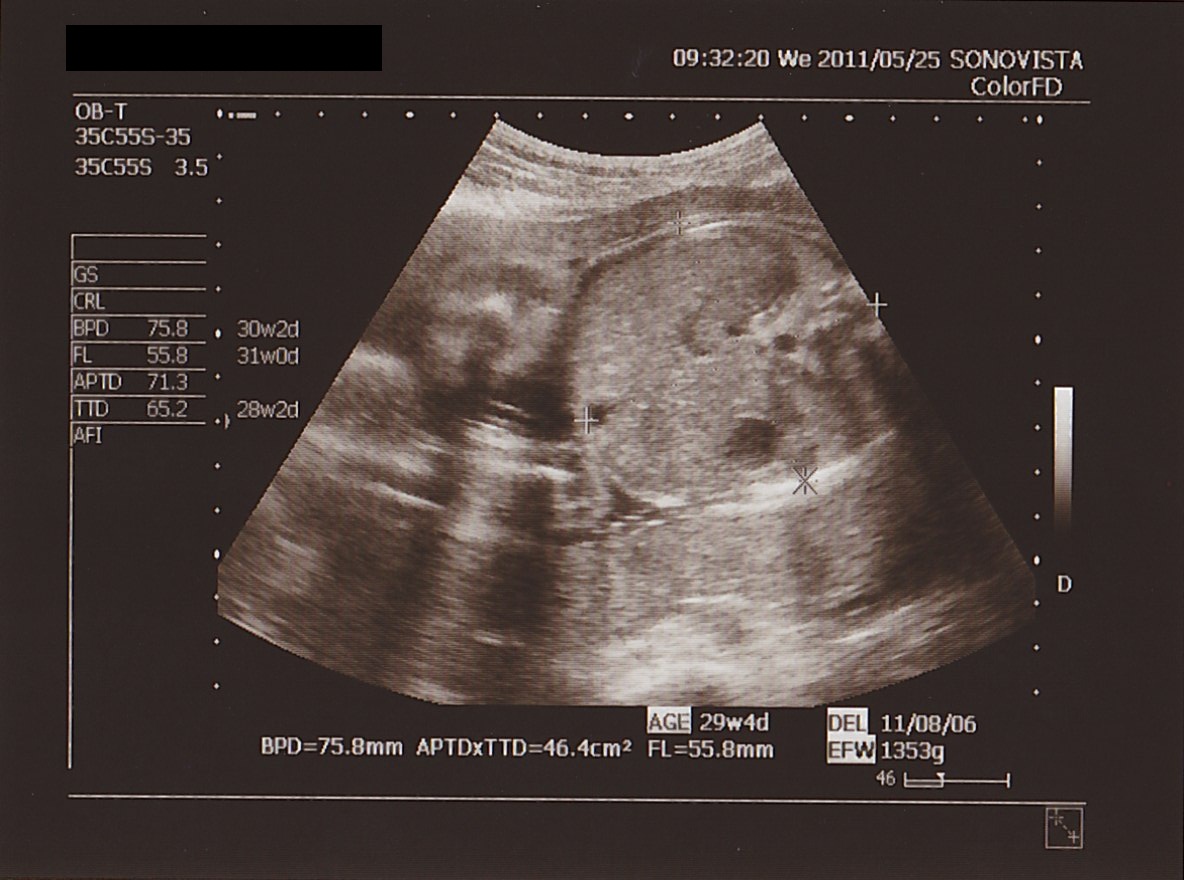

▲ まんまる お腹を 計測です。

この日の 測定値は

BPD ( 頭の直径 ) : 75.8ミリ

APTD × TTD ( お腹まわり ) : 46.4平方センチメートル

FL ( 太もも骨長 ) : 55.8ミリ

EFW ( 推定体重 ) : 1353グラム

でした。

この結果で 想定週数が 29w 4d と 出て

実際の 週数より ちょうど 1週間オーバー。

せんせいは

「今回は ちょっと 大きめだね。

でも とくに 問題ない範囲だから だいじょうぶ」

とのこと。